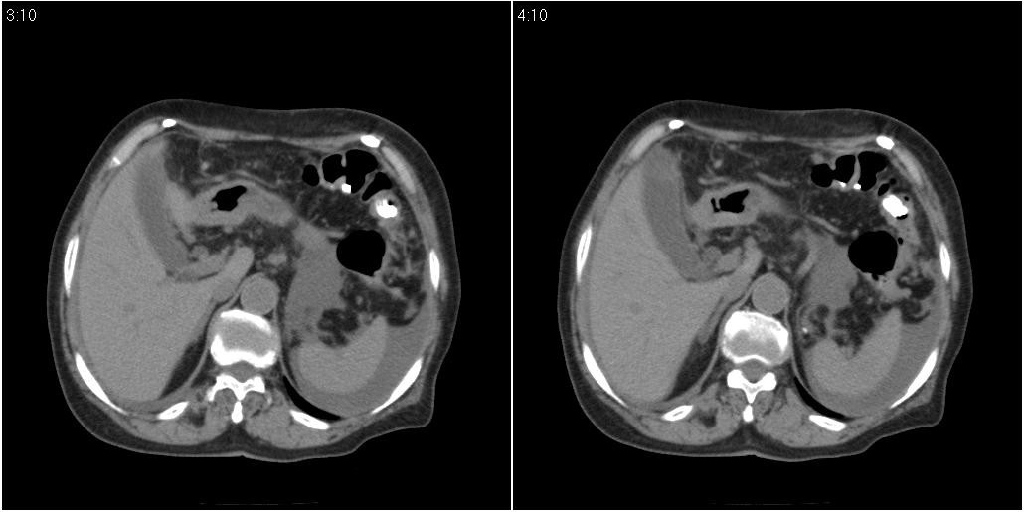

胆囊有问题么,是结石么?胆囊内异常密度平扫30hu左右,增强各期无变化。

胆囊炎,胆结石,胆囊窝积液,胸腹水。

胆囊内稍高密度影,无强化,胆囊壁增厚,周围见低密度影,右侧膈肌角及脾周水样密度,支持胆囊泥沙样结石,胆囊炎、胆囊窝积液,胸腹水。

1)胆囊炎,胆结石;胆囊新生物待排。2)胆囊窝积液。3)腹水。4)右侧少量胸腔积液。